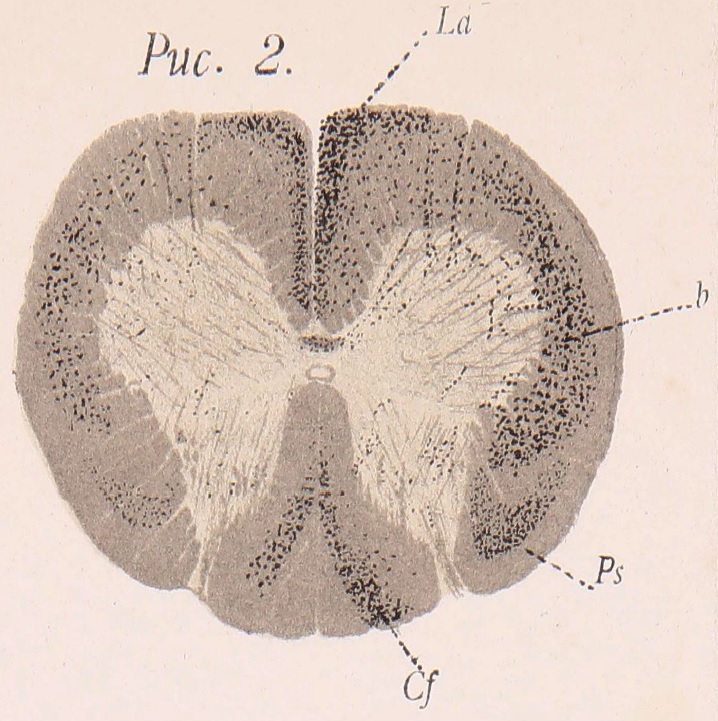

На уровнѣ 2-ой пары шейныхъ корешковъ: Перерожденіе въ пучкахъ Голля выражено слабо и почти одинаково на обѣихъ сторонахъ. По серединѣ задняго столба оперированной стороны идетъ перерожденная полоса, густо усѣянная черными глыбками и начинающаяся спереди отъ задней спайки, а кзади достигающая периферіи мозга, гдѣ она подъ угломъ поворачиваетъ кнаружи, не доходя, однако, до зоны Lissauer’a. Въ заднемъ столбѣ противоположной стороны наблюдается подобная же полоса черныхъ глыбокъ распавшагося міэлина, но только количество ихъ значительно меньше и онѣ не такъ интенсивно окрашены (Табл. II, рис. 1). Въ боковомъ столбѣ на сторонѣ перерѣзки перерожденіе идетъ по периферіи и наиболѣе выражено въ заднемъ его отдѣлѣ, отвѣчающемъ пучку Flechsig’a. Этотъ пучекъ имѣетъ здѣсь форму запятой, головка которой обращена кзади; передняя часть его на высотѣ задней спайки суживается и незамѣтно переходитъ въ краевое перерожденіе, идущее по передне-боковой поверхности мозга. Это краевое перерожденіе представляется уже болѣе разсѣяннымъ и въ вентральномъ направленіи по окружности мозга достигаетъ мѣста выхода переднихъ корешковъ; на высотѣ центральнаго канала это краевое перерожденіе нѣсколько расширяется, причемъ черныя глыбки задаются вглубь бѣлаго вещества мозга, образуя выступъ треугольной формы. На противоположной сторонѣ въ боковомъ столбѣ наблюдаются лишь отдѣльныя перерожденныя волокна, располагающіяся, главнымъ образомъ, по периферіи его задняго и передняго отдѣловъ. Въ переднихъ столбахъ совершенно нѣтъ перерожденныхъ волоконъ. Въ сѣромъ веществѣ мозга той и другой стороны можно обнаружить черныя глыбки, идущія цугами изъ заднихъ столбовъ и, огибая снаружи столбы Клярка, направляющіяся къ основанію переднихъ роговъ. Изъ задней части прямыхъ мозжечковыхъ пучковъ также идутъ перерожденныя волокна, направляющіяся косвенно черезъ основаніе заднихъ роговъ и переходящія, повидимому, черезъ переднюю спайку въ передній рогъ противоположной стороны. Въ передней спайкѣ наблюдаются черныя тонкія жилки и отдѣльныя мелкія глыбки распавшагося міэлина (рис. 1, с).

Въ нисходящемъ направленіи. На уровнѣ 6-ой пары шейныхъ корешковъ: въ пучкахъ Голля совсѣмъ не наблюдается черныхъ глыбокъ; пучки Бурдаха перерождены въ ихъ внутренней части, идущей по границѣ съ пучками Голля, причемъ перерожденіе на сторонѣ перерѣзки выражено рѣзче, чѣмъ на противоположной. Эта перерожденная область идетъ въ видѣ дуги, вогнутостью обращенной кнаружи; передній конецъ этой дуги немного не доходитъ до задней спайки; задній конецъ на сторонѣ перерѣзки достигаетъ задней периферіи мозга, а на противоположной нѣсколько не доходитъ (табл. II, рис. 2, Cf). Вся периферія боковыхъ столбовъ на обѣихъ сторонахъ совершенно свободна отъ черныхъ глыбокъ, тогда какъ внутренніе ихъ отдѣлы, прилегающіе къ сѣрому веществу, густо усѣяны черными глыбками неодинаковаго калибра, причемъ въ заднихъ частяхъ боковыхъ столбовъ, въ области, отвѣчающей мѣсту расположенія боковыхъ пирамидныхъ пучковъ, эти глыбки представляются болѣе мелкими, чѣмъ въ переднихъ частяхъ. Въ вентральномъ направленіи перерожденная область въ боковыхъ столбахъ достигаетъ переднихъ корешковъ и даже переходитъ нѣсколько въ предѣлы переднихъ столбовъ, огибая передній край переднихъ роговъ. На сторонѣ, противоположной перерѣзкѣ, описанное перерожденіе въ боковыхъ столбахъ выражено сравнительно слабѣе (табл. II, рис. 2). Въ переднихъ столбахъ черныя глыбки сравнительно крупнаго калибра идутъ по ихъ передней периферіи и вдоль передней вырѣзки, вплоть до передней спайки. Это краевое перерожденіе въ переднихъ столбахъ на сторонѣ перерѣзки выражено нѣсколько рѣзче, чѣмъ на противоположной. Въ передне-наружныхъ отдѣлахъ переднихъ роговъ наблюдаются черныя глыбки, а мѣстами черныя тонкія жилки, направляющіяся въ боковые и въ передніе столбы. Передніе корешки на пути ихъ хода въ бѣломъ и въ сѣромъ веществѣ мозга также содержатъ черныя глыбки распавшагося міэлина; таковыя же мелкія глыбки наблюдаются и въ передней спайкѣ (рис. 2).